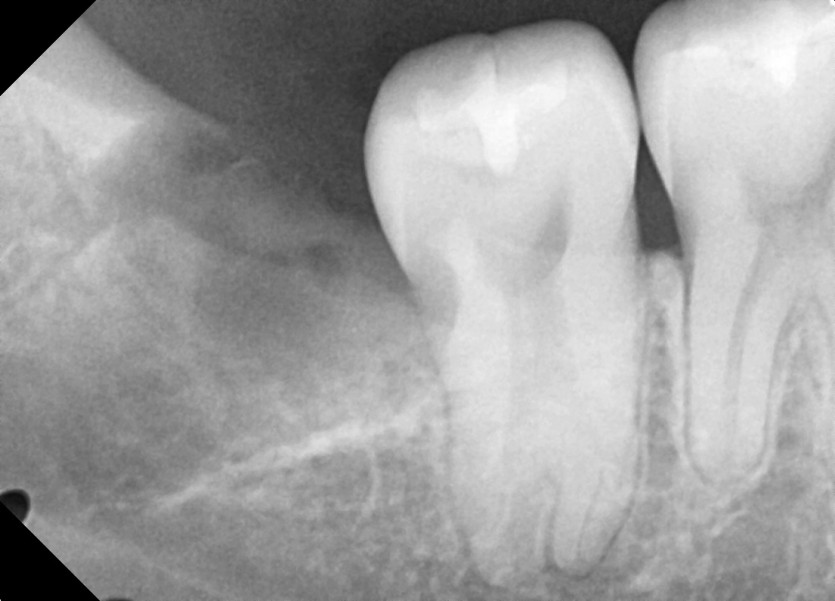

#48 사랑니 발치

구강 외과 전문의가 당일 발치했습니다.